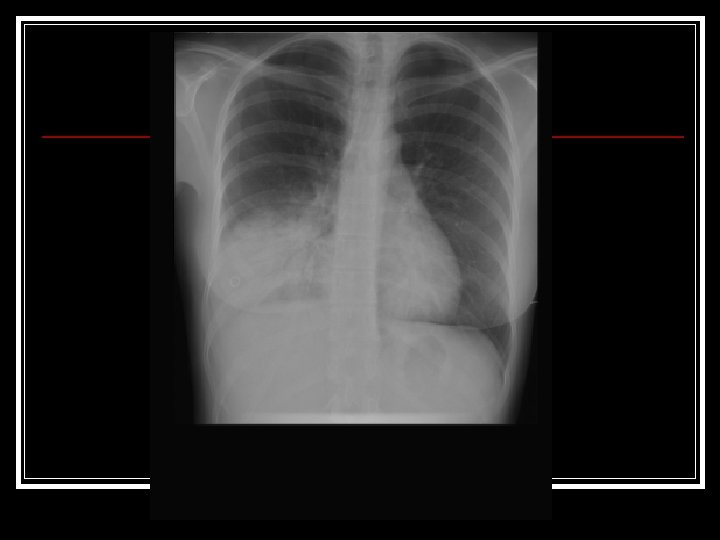

Le patient décrit: Une dyspnée de survenue brutale, la veille au soir n Avec une fièvre élevée et des frissons n Douleur basithoracique droite d’apparition brutale n Une toux avec des expectorations purulentes « rouillées » apparues ce matin n

A l’examen physique, on retrouve: n n n n Absence de signes de gravité Majoration des vibrations vocales en base droite Matité en base droite Souffle tubaire en base droite Entouré d’un foyer de crépitants BDC réguliers, sans souffle Absence de signe d’insuffisance cardiaque droite Absence de signe de phlébite

Hypothèses diagnostiques? n Pneumopathie infectieuse de la base pulmonaire droite (le plus probable) n - Diagnostiques différentiels devant une dyspnée aigue: Exacerbation aigue de BPCO Syndrome de Détresse Respiratoire Aigue Embolie pulmonaire (possible) Œdème aigu pulmonaire (contexte clinique non correspondant) Epanchement pleural abondant (contexte clinique non correspondant) Pneumothorax (contexte clinique non correspondant)

Dans ce contexte vous devez demander les examens complémentaires suivants: Bilan biologique: NF, PCR, PCT, Iono sanguin, urée, créatininémie, bilan hépatique n Gazométrie artérielle n ECG n Radiographie de thorax n